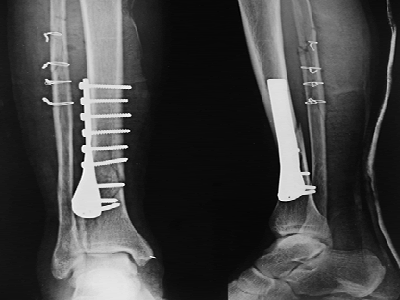

胫腓骨骨折X光图(资料图,与卢克-肖无关)

在足球场上,这其实还算是一种并不罕见的重伤伤情。《泰晤士报》医疗专家马克-波特博士就说:“这是足球界最常见的长骨伤情。”情节较轻的骨折,也许不需要手术,打上石膏等待自然愈合。但如果伤处不稳定,就需要固定:要么就是外部用支架,要么就是内部用特殊的钉子、金属板、金属棒或螺丝来固定。后者的康复速度会快一点,但不管怎样都存在愈合不良的风险。